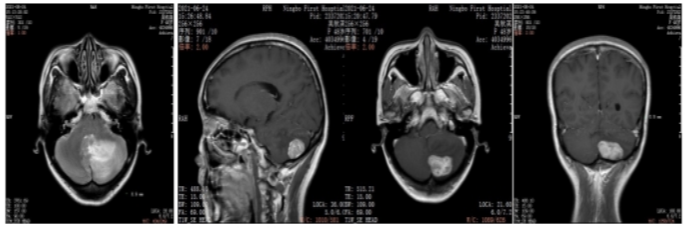

2021年6月颅脑增强MRI:左侧小脑占位,考虑转移瘤。

图2.颅脑增强MRI

2021年6月:出现头晕头痛1周,检查颅脑增强MRI:左侧小脑占位,考虑转移瘤。